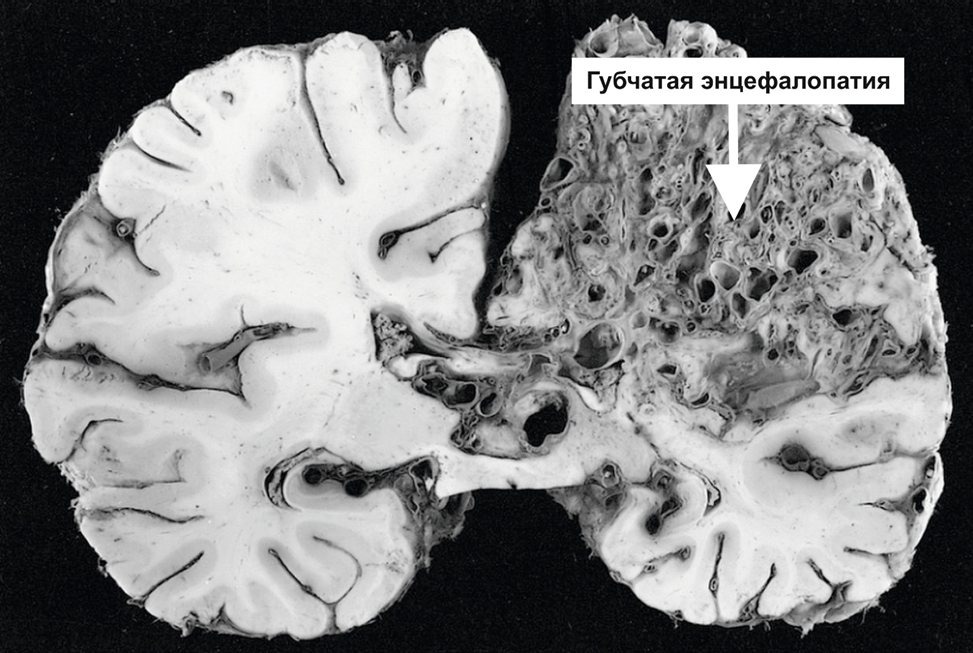

Прионы (от англ. proteinaceous infectious particle) — это инфекционные белки, способные вызывать смертельные дегенеративные заболевания головного мозга. В отличие от вирусов и бактерий, прионы не содержат генетического материала (ДНК или РНК) — это просто белки, которые «перевоспитывают» нормальные белки организма в свои копии.

Процесс напоминает цепную реакцию: один «испорченный» прион встречается с нормальным белком PrP^C (прионовый белок клетки) и превращает его в патологическую форму PrP^Sc. Новые прионы накапливаются в нервной ткани, образуя амилоидные бляшки, разрушающие нейроны.